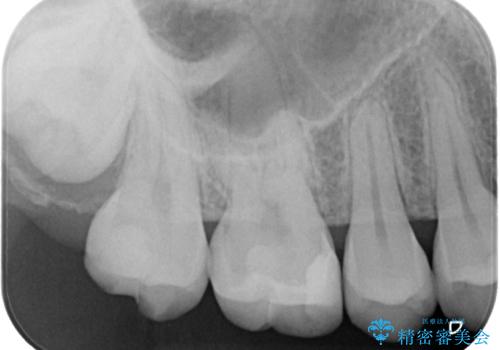

- 銀歯の詰め物が外れてしまったので、これを機にセラミックにやり替えたいと来院されれた患者様です。

虫歯になってしまっているところをしっかりと除去し、形を整えて、精度の高いシリコーンによる型どりを行いました。

また、インレー接着時には唾液や血液による接着力の低下を防ぐためにラバーダム防湿を行っています。

精度の高い詰め物は二次的な齲蝕になりにくいです。